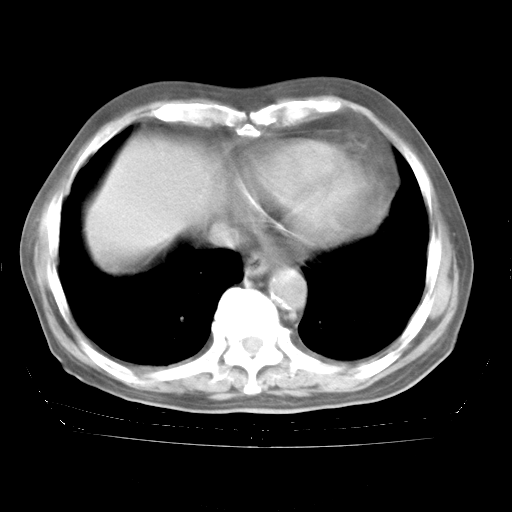

4月28日肺部CT——再次出现类似去年5月9日——透光度降低,“间质性”改变。

4月28日肺部CT——再次出现类似去年5月9日——磨玻璃样、间有“粟粒样”改变。